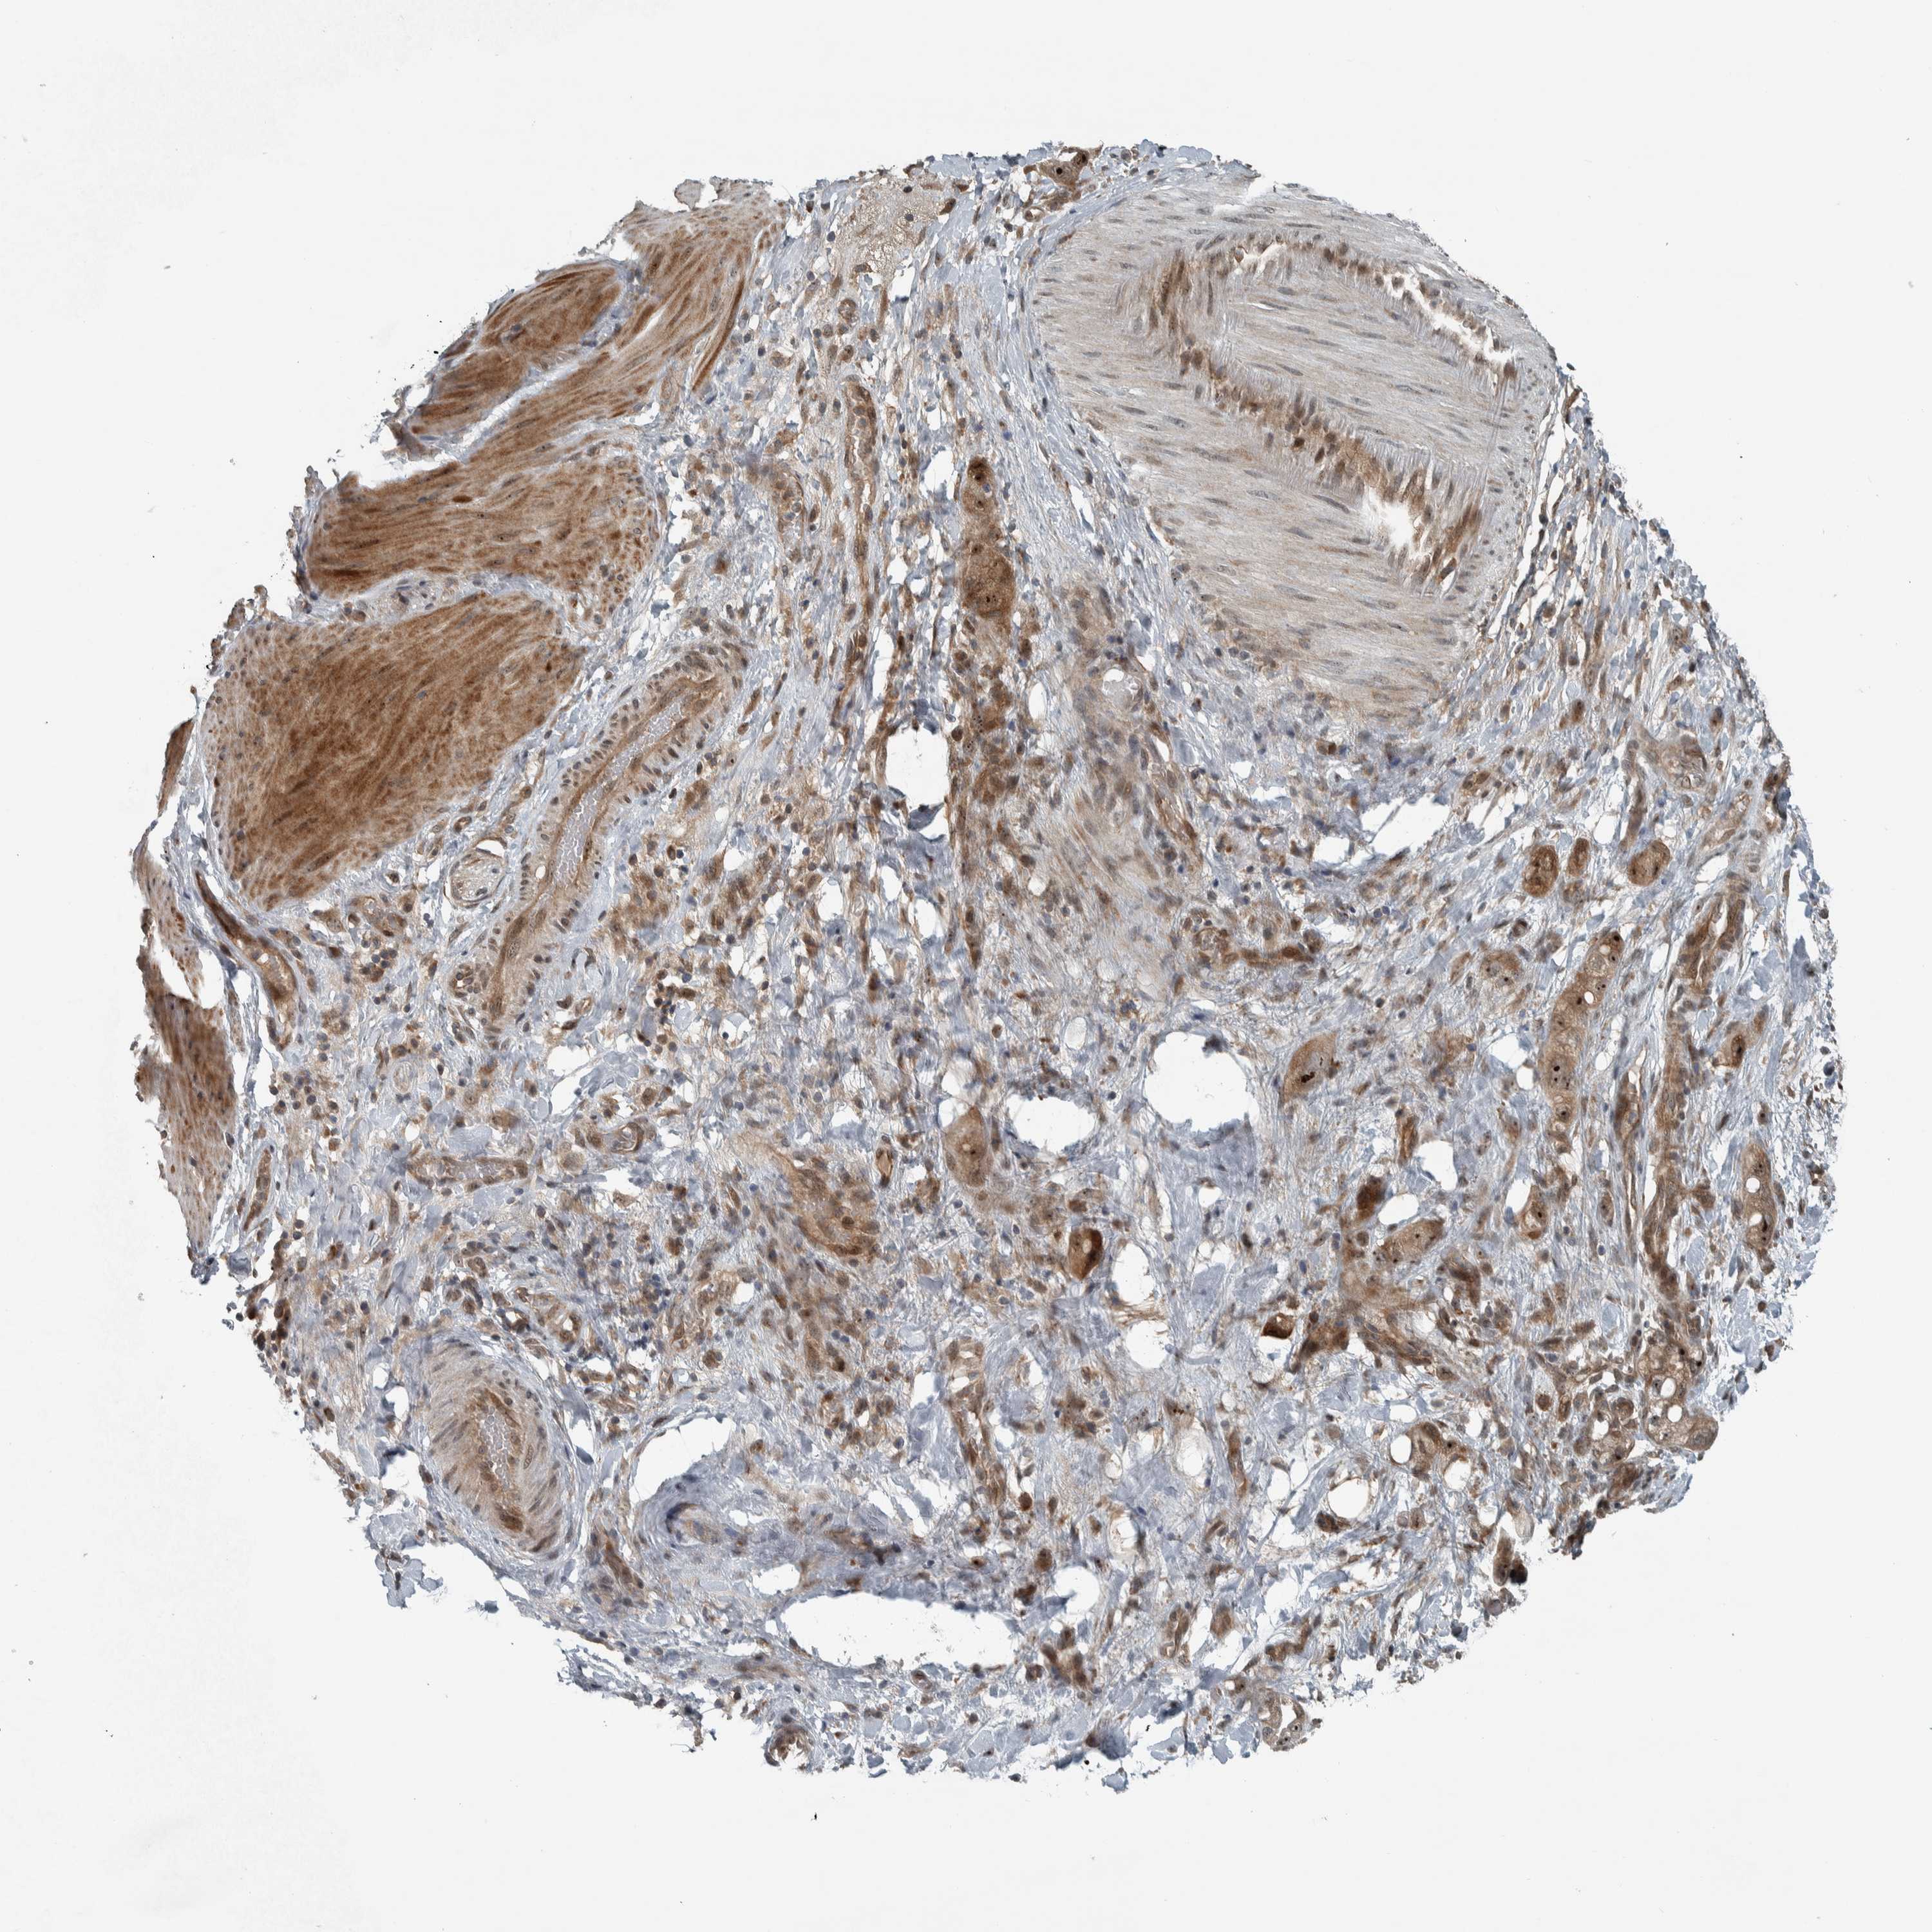

STOMACH CANCER - Protein expressioni

A mouse-over function shows sample information and annotation data. Click on an image to view it in a full screen mode. Samples can be filtered based on level of antibody staining by selecting one or several of the following categories: high, medium, low and not detected. The assay and annotation is described here.

Note that samples used for immunohistochemistry by the Human Protein Atlas do not correspond to samples in the TCGA dataset.

Antibody stainingi

Antibody staining in the annotated cell types in the current human tissue is reported as not detected, low, medium, or high, based on conventional immunohistochemistry profiling in selected tissues. This score is based on the combination of the staining intensity and fraction of stained cells.

Each image is clickable and will lead to virtual microscopy that enables deeper exploration of all samples and also displays staining intensity scores, fraction scores and subcellular localization as well as patient and tissue information for each sample.

Antibody HPA018402

Antibody HPA023959

Staining

High

Medium

Low

Not detected

Intensity

Strong

Moderate

Weak

Negative

Quantity

>75%

75%-25%

<25%

None

Location

Nuclear

Cytoplasmic/membranous

Cytoplasmic/membranous,nuclear

Adenocarcinoma, NOS